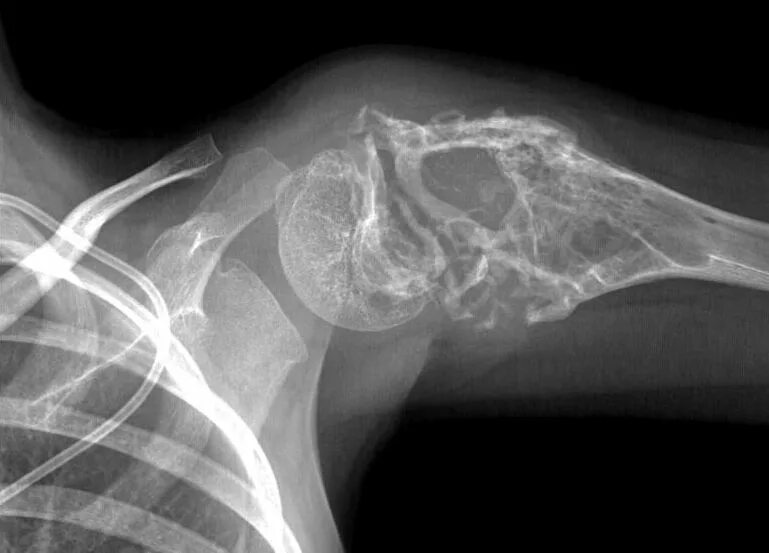

Метастазы в ключице